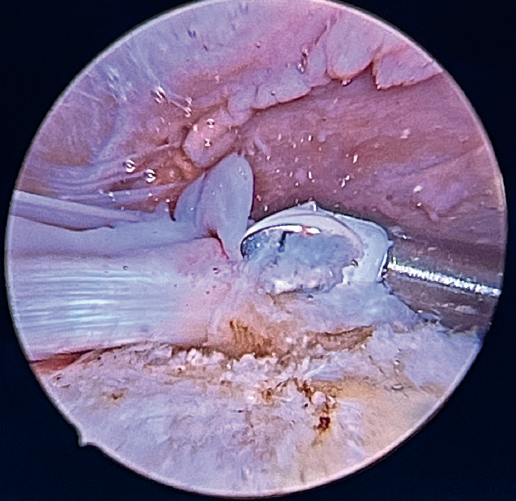

Previously, at intra-articular level, we assessed the quality of the LPB and its insertion in the supraglenoid tuberosity; from subacromial, having prepared the bony footprint on the greater tuberosity, we proceed to release the proximal portion of the tendon from the bicipital groove. The upper part of the transverse humeral ligament is sectioned to mobilize the LPB without damaging it (Figure 2). At this time, the mobility and integrity of the LPB is checked with tendon pulling forceps (Figure 3).

The glenoid origin of the LPB is preserved at all times. In the anterolateral zone of the greater tuberosity, we implant an anchor loaded with three sutures (FiberTak® 2.6 mm, Arthrex, Naples, FL, USA), more medial to the reflection zone of the LPB. To ensure correct guidance at implantation, we create a superolateral accessory portal without a cannula, close to the limit of the acromion.

Using penetrating forceps through the anterior portal, the surgeon penetrates the LPB and retrieves one of the suture threads, performing a self-locking Lasso suture in the same step. This is done with two of the three anchoring threads to ensure a correct LPB grip to the footprint of the greater tuberosity and that the tendon does not fray; we do not cut the two threads after knotting (Figures 4, 5 and 6). We also consider it very important to apply the biceps tendon, keeping it as flat and anatomical as possible, avoiding twisting or excessive distension of the tendon. Subsequently, a tenotomy of the LPB distal to these sutures is performed (Figure 7), thus allowing the LPB to function as a superior capsular reconstruction, restricting the ascent of the humeral head.